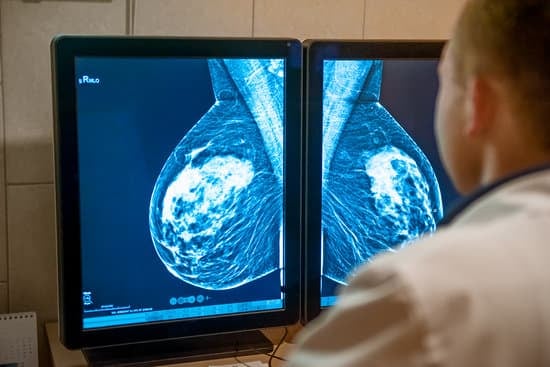

주로 유방암 진단과 양성 종양 제거에 사용되며, 초음파나 X-ray 같은 영상 장비를 이용해 정확한 위치에서 조직을 채취할 수 있습니다.

사전 준비: 시술 전 초음파 또는 맘모그래피를 통해 종양의 위치를 확인합니다.